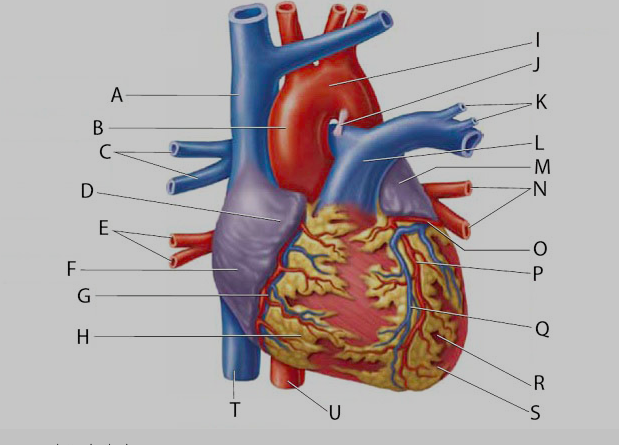

Anterior interventricular valve

Anterior interventricular sulcus

Posterior interventricular sulcus

Aortic Arch

Aortic Valve (=left semilunar)

Apex (of the heart)

Brachiocephalic artery

Brachiocephalic vein

Circumflex branch (of the left coronary artery)

Coronary sinus

Endocardium

Epicardium

interventricular branch of the left coronary artery. = left anterior descending artery (LADA))

Left atrioventricular (=bicuspid, =mitral) valve

Left/right atrium

B & F

Left/right auricle

Left/right coronary artery

left/right pulmonary artery/vein

left/right ventricle

Myocardium

Papillary muscles

Pectinate muscles

Pulmonary trunk

Pulmonary valve (=right semilunar)

Right atrioventricular (=tricuspid) valve

Right coronary vein

Superior/inferior vena cava